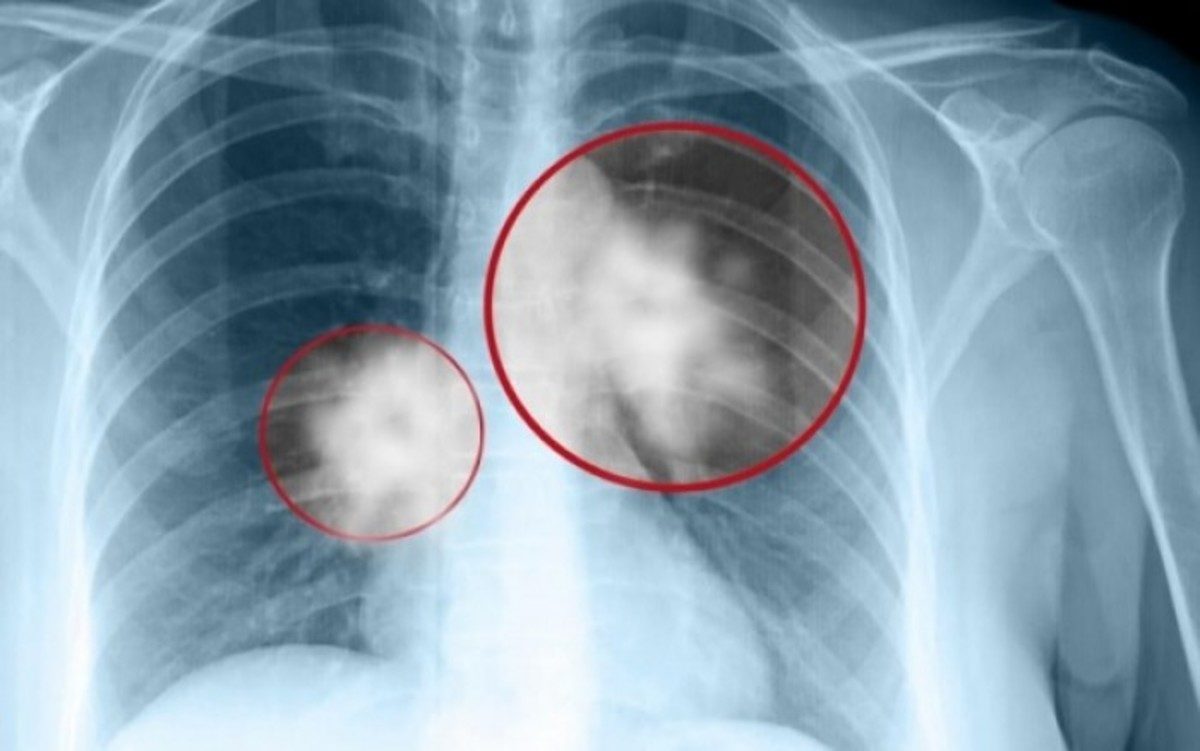

Το 80% του καρκίνου των πνευμόνων προέρχεται από το κάπνισμα. Τα παιδιά που καπνίζουν σήμερα, κατά τα επόμενα τριάντα χρόνια θα αντιμετωπίσουν πολύ σοβαρό πρόβλημα. "Θα πρέπει να κάνουμε κάτι", σκέφτηκε πριν από μερικά χρόνια που επισκέφτηκε την Αθήνα, ο Έλληνας ερευνητής που ζει στις ΗΠΑ, Γεώργιος Μπεχράκης, επίτιμος διδάκτορας του τμήματος Ιατρικής της Σχολής Επιστημών Υγείας του Παν. Αθηνών, ερευνητής Φαρμακολογίας, που χορηγεί στην Ελλάδα προγράμματα για την διακοπή του καπνίσματος .

-«Όλα ξεκίνησαν στη διάρκεια ενός ταξιδιού μου στην Ελλάδα και λόγω των διαδηλώσεων στο κέντρο της Αθήνας, έμεινα σ’ ένα μικρό ξενοδοχείο στην Κηφισιά. Ένα πρωινό περπάτησα στην περιοχή, γύρω από το ξενοδοχείο, κι έτυχε να περάσω μπροστά από ένα σχολείο οπότε είδα δύο μαυροντυμένες γυναίκες να δίνουν δωρεάν τσιγάρα σε μικρά κορίτσια. Τις πλησίασα διότι ήθελα να δω τι έκαναν, δεν μιλούσαν ούτε ελληνικά, ούτε αγγλικά, αλλά μοίραζαν τσιγάρα σε κοριτσάκια 11 και 12 χρονών. Τηλεφώνησα στον εξάδελφό μου, τον Παναγιώτη Μπεχράκη, ο οποίος είναι γιατρός πνευμονολόγος και καθηγητής στο Πανεπιστήμιο και τον ρώτησα τι γίνεται εδώ; Επιτρέπει η κυβέρνηση σε αλλοδαπούς να μοιράζουν τσιγάρα σε μικρά κορίτσια και αγόρια; Θα αντιμετωπίσετε μεγάλη καταστροφή στα επόμενα τριάντα χρόνια. Εσύ που είσαι γιατρός γνωρίζεις ότι το 80% του καρκίνου των πνευμόνων προέρχεται από το κάπνισμα των τσιγάρων. Αυτά τα παιδιά θα καπνίζουν κατά τα επόμενα τριάντα χρόνια και θα προκύψει πολύ σοβαρό πρόβλημα. Θα πρέπει να κάνουμε κάτι» Η Ελλάδα ήταν η νούμερο ένα χώρα στην Ευρώπη, δαπανώντας δισεκατομμύρια στην αγορά καπνού. Η εκστρατεία κατά του καπνίσματος είχε ως αποτέλεσμα η Ελλάδα να πέσει από την πρώτη, στην τρίτη θέση του ευρωπαϊκού χάρτη καπνίσματος. Βεβαίως, και η αύξηση της φορολογίας στα τσιγάρα έχει βοηθήσει πολύ. Πάνω από όλα όμως είμαι πολύ εντυπωσιασμένος μ’ αυτά τα παιδιά, τα Ελληνόπουλα. Είναι πολύ επιδεκτικά μαθήσεως και έχουν γνώσεις».

-Στις γυναίκες θα έδειχνα στατιστικές εγκυμοσύνης. Στους άντρες θα εξηγούσα πόσο επιζήμιο είναι το κάπνισμα. Το σώμα δεν μπορεί να απορροφήσει μη φυσικά προϊόντα, ούτε να μεταβολίσει τις πρόσθετες ουσίες ενός τσιγάρου. Ο καλύτερος τρόπος για να πειστεί κάποιος να κόψει το κάπνισμα, είναι η εκπαίδευση, δείχνοντας τη θανάσιμη δύναμη του καπνού.